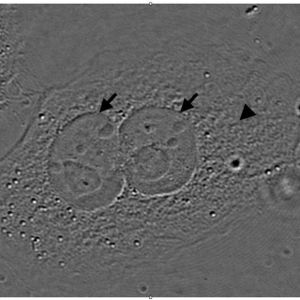

El primer paso de la tecnología del trasplante nuclear constituyó así mismo el primer paso de la clonación y lo dio un investigador inglés llamado John Gurdon a finales de los años sesenta, en unos anfibios. Los experimentos de Gurdon en la especie de sapo Xenopus laevis, consistieron en el trasplante de núcleos desde células somáticas procedentes del epitelio intestinal de renacuajos a óvulos no fecundados de la misma especie, a los que previamente se había eliminado el núcleo. Tras el reemplazo del núcleo gamético del óvulo por el núcleo somático, los embriones así formados se activaban y empezaban a crecer de forma aparentemente normal mediante la proliferación celular hasta alcanzar el estado de blastocisto, como si de un embrión natural se tratara.

A continuación, Gurdon procedió a la disociación de las células del blastocisto, los blastómeros, de los que se extraían de nuevo los núcleos para implantarlos en una serie de óvulos enucleados de la misma especie. El desarrollo de los embriones formados de esta manera daba lugar a un clon de individuos, que resultaron genéticamente idénticos entre sí e idénticos al individuo del que procedía el núcleo de la célula epitelial inicial. Es importante señalar que, al margen de la curiosidad de la creación de estos clones, lo que aquellos experimentos demostraban era la importancia de la información genética contenida en el núcleo celular trasplantado, cuyo genoma se revela como el gran centro coordinador del desarrollo de un nuevo ser.

También es importante decir que en estos experimentos solo una pequeña proporción de los embriones producidos fueron viables, lo que demostraba que las condiciones en que se realizaban los trasplantes de núcleos, el estado de los óvulos y las manipulaciones que todo esto conllevaba, originaban problemas para el normal desarrollo de algunos de los embriones producidos.